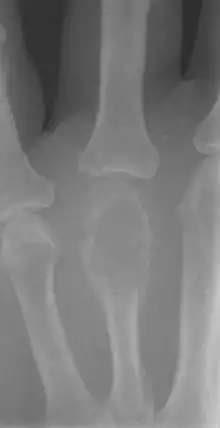

| Non-ossifying fibroma of tibia | |

The most common bone tumor is a non-ossifying fibroma.[4] Average five-year survival in the United States after being diagnosed with bone and joint cancer is 67%.[5] The earliest known bone tumor was an osteosarcoma in a foot bone discovered in South Africa, between 1.6 and 1.8 million years ago.[6]